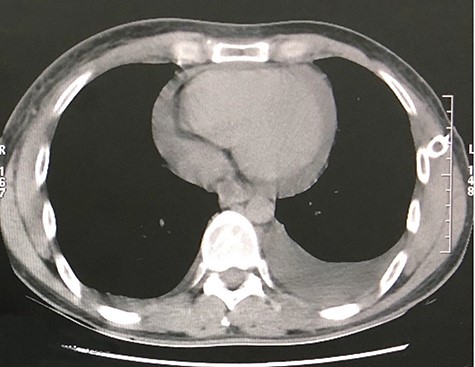

The first case consists of a 26-year-old male that presented with dyspnoea at rest, tachycardia, jugular vein distention, and slight facial and upper limb edema. The patient had been previously treated with ceftriaxone and moxifloxacin, and underwent a left thoracostomy due to a chest radiograph that showed a pleural effusion in the left inferior hemithorax. At auscultation, the patient had reduced air entry in the left lung base. The patient did not show improvement with the treatment previously given, so new laboratory tests were ordered. The blood test showed an elevated lactate dehydrogenase at 652 U/L and the pleural fluid analysis showed an elevated lactate dehydrogenase at 911 U/L, cholesterol level at 46 mg/dl, and triglyceride level at 847 mg/dl. According to these results, the pleural effusion was classified as an exudate. The high triglyceride level was consistent with a chylous effusion. A chest CT confirmed a pericardial effusion, the previously noticed free pleural effusion, and an irregular mass in the anterior mediastinum with heterogeneous density that included hypodense areas that suggest necrosis (Figs 1 and 2). Subsequently, the patient underwent surgical treatment, which consisted of a pericardial window. Aside from this procedure, the anterior mass was biopsied. Histological analysis revealed a non-Hodgkin lymphoma. Due to the diagnosis, the patient was transferred to the hematology care unit to receive chemotherapy, but he continued to deteriorate and passed away 2 months later.

CT scan axial view of a pericardial and left lung pleural effusion.